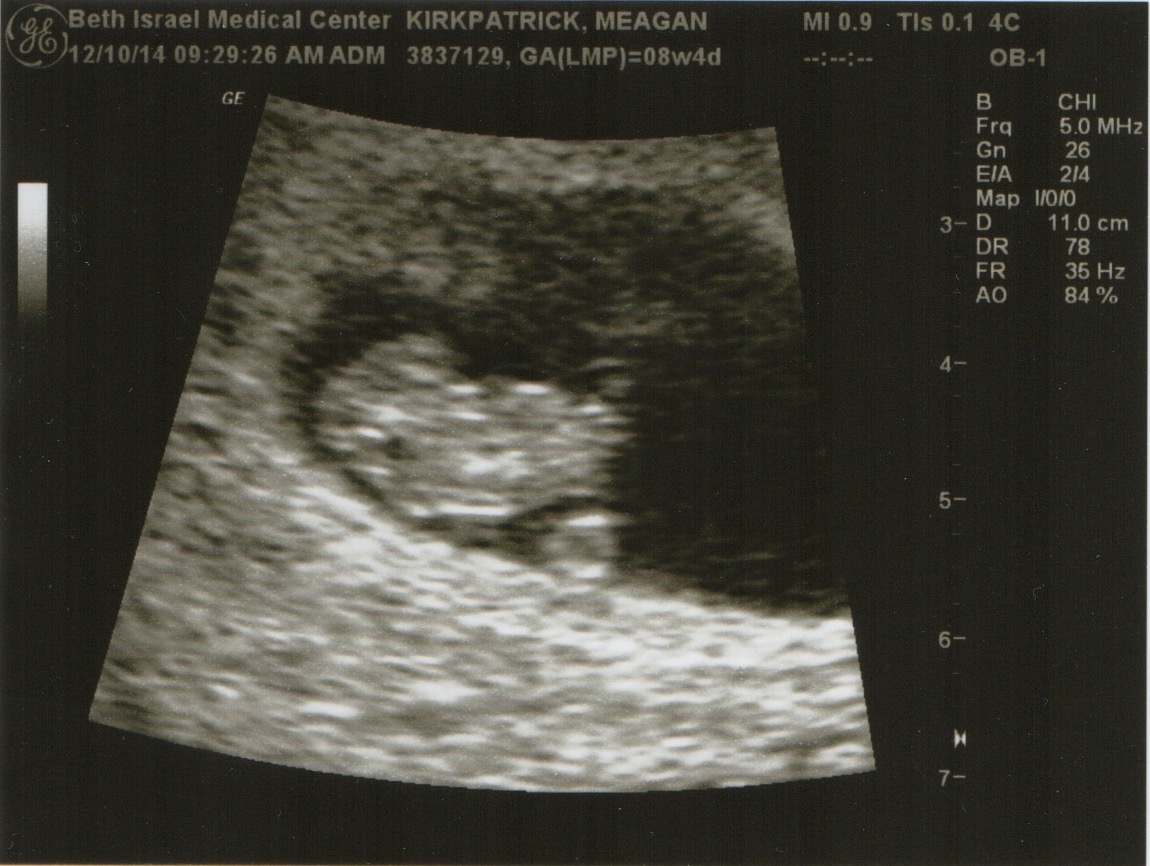

But this year felt like an almanac of news I had to cram into one tiny card: falling in love, leaving my job, heading off to Europe, planning a move to California, and most importantly, expecting a little one. So being the digitally savvy folks we are, we thought we’d break the monotony and create this little blog to keep everyone more up to date.

Meagan + Jimmy (+ Baby!)